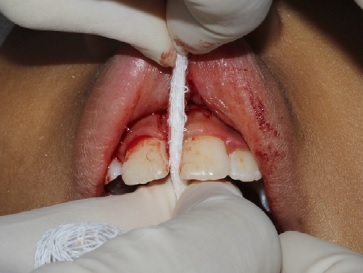

Em seguida, foi realizado o pinçamento na posição apical do freio com a pinça hemostática Kelly e foram efetuadas duas incisões verticais com lâmina de bisturi n.º 15c (Solidor, Brasil) em forma de “v”, com incisão no fundo de sulco até a região da papila interincisiva para a remoção do freio labial superior em nível supra periosteal (Figura 2‑3-4-5).

Essa papila interincisiva foi preservada para não provocar um espaço negro (black space). Após a remoção do tecido fibroso entre o segmento interdental e a papila interincisiva na região palatina, foi realizado um debridamento com gaze (Cremer, Brasil), ou seja, uma fenestração óssea (Figura 6), fazendo uma pequena fricção entre os dentes para remover as fibras mais internas que estavam em contato com o osso. Em seguida, foi feito a divulsão dos bordos, isto é, um descolamento do tecido mucoso em relação ao tecido muscular e remoção de fibras que se encontravam unidas ao osso. Esse procedimento foi feito com a pinça Dietrich para pinçamento dos bordos, inserção da tesoura sempre fechada dentro do tecido e só era aberta dentro do plano mucoso, fazendo a divulsão dos tecidos. Foram encontradas algumas glândulas salivares menores e estas foram removidas.